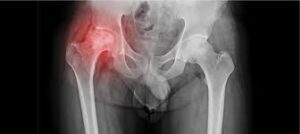

Avascular necrosis, commonly known as AVN, is a condition where reduced blood supply leads to damage of bone tissue, most often affecting the hip joint. Therefore, timely AVN treatment Adilabad is essential to prevent joint collapse and long-term disability. Patients may initially notice pain during movement, which can gradually worsen if left untreated. In Adilabad, structured orthopedic evaluation and planned treatment approaches help patients manage AVN effectively and preserve joint function.

AVN develops when bone tissue does not receive sufficient blood flow. Consequently, the affected bone weakens and may lose its structural integrity over time. AVN treatment Adilabad focuses on slowing disease progression and maintaining joint stability. Moreover, early diagnosis allows for better preservation of natural joint movement. Awareness of symptoms such as persistent hip pain or stiffness plays a key role in timely medical attention.

The hip joint is most commonly affected. Other joints may also be involved in some cases.